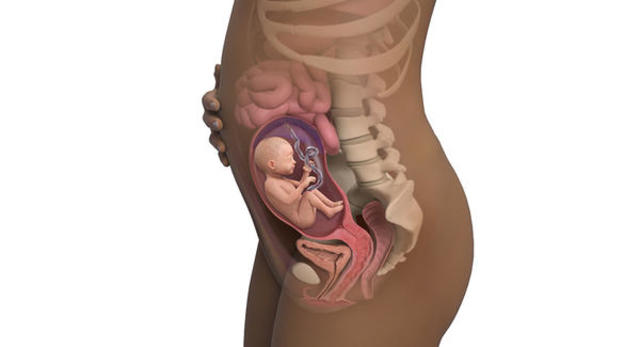

• Desarrollo fetal

Esta etapa comienza desde el momento en que se ha completado la etapa embrionaria, y hasta que se produzca el parto. Durante la vida fetal no se forman órganos o tejidos nuevos, sino que se produce la maduración de los ya existentes. Al finalizar la décima semana de edad gestacional el embrión ha adquirido su forma básica y el siguiente período es el del desarrollo fetal, cuando los órganos se desarrollan completamente

• Semanas 9 a 12

Semanas 9 a 12

Los párpados se cierran y no se vuelven a abrir casi hasta la semana 28

La cara está bien formada

Las extremidades son largas y delgadas

Los genitales aparecen bien diferenciados

Los glóbulos rojos se producen en el hígado

El tamaño de la cabeza corresponde casi a la mitad del tamaño del feto

El feto puede empuñar los dedos

Aparecen los brotes dentarios